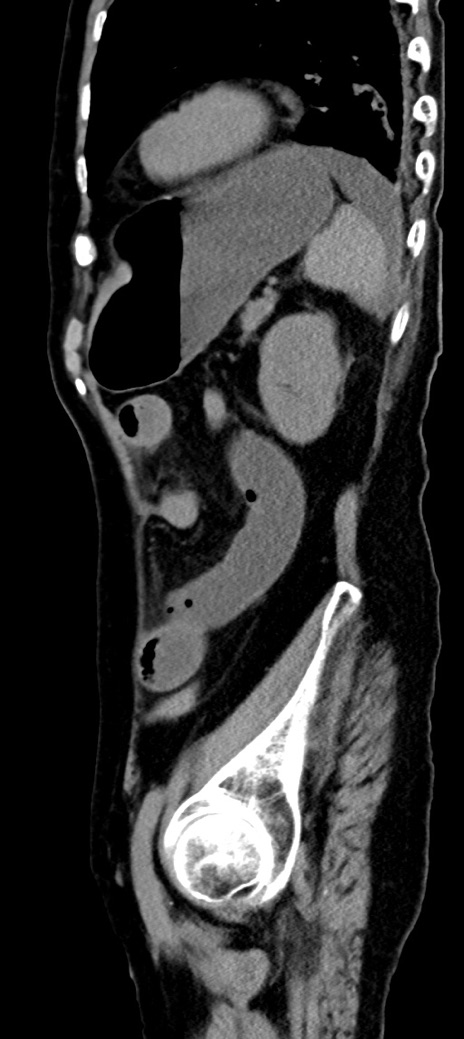

症例40(矢状断像)他院1日前

【症例】90歳代女性

【主訴】腹痛・嘔吐

【現病歴】 食欲低下、嘔吐があり昨日他院受診。肺炎と診断され入院となる。入院後より腹部全体に圧痛あり。胃管留置され経過みていたが、症状持続するため、

当院転院となる。

【既往歴】胸椎圧迫骨折、胆石症

【身体所見】腹部:中央に激痛あり、圧痛あり、反跳痛不明

【データ】WBC 17100、CRP 18.82